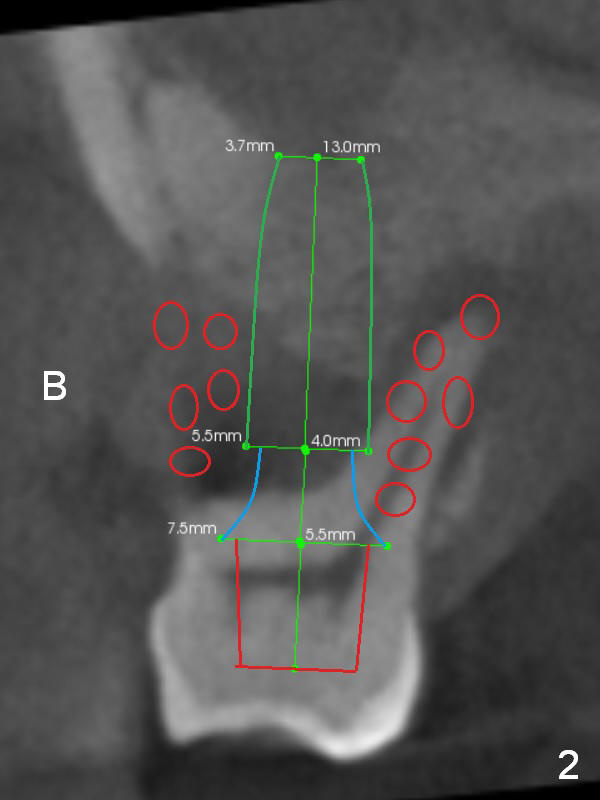

It may take 6 months for #19 implant re-placement after socket preservation. The tooth #3 is symptomatic (Fig.1). In spite of implant failure at #19, the best treatment for #3 of the same patient is still immediate implant. Previous practice is to place an implant as long as possible (Fig.2). The coronal threads are not covered by the native bone. Bone graft (red circles) cannot guarantee thread coverage. Periimplantitis may develop more likely in periodontitis patients if bone graft is not tightly packed.

A safe method is to use a shorter implant and place it as deep as possible so that the majority of the threads are subcrestal (Fig.3 green). Pack bone graft tightly (smaller red circles) and also check whether there is a piece of gauze in the socket prior to grafting. The corresponding changes are to place a long abutment with long cuff (7.5x7(5) mm). Bone density is relatively low. Prepare bone expanders.